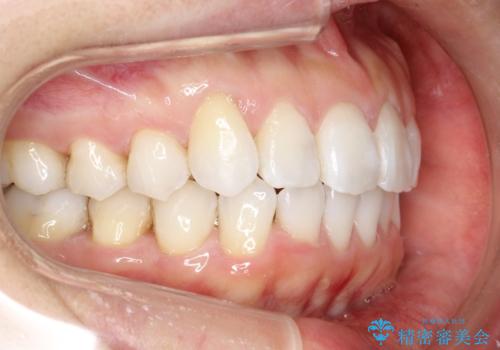

抜歯せずに八重歯のマウスピース矯正

- 1年3ヶ月

- 非抜歯・遠心移動+IPR+拡大 によるマウスピース矯正を計画した。

八重歯がシビアな場合、抜歯をしないと治せないケースもありますが、奥歯の位置関係を修正したり、歯のサイズダウンを行うことで、抜歯をせずに改善できる場合もたくさんあります。